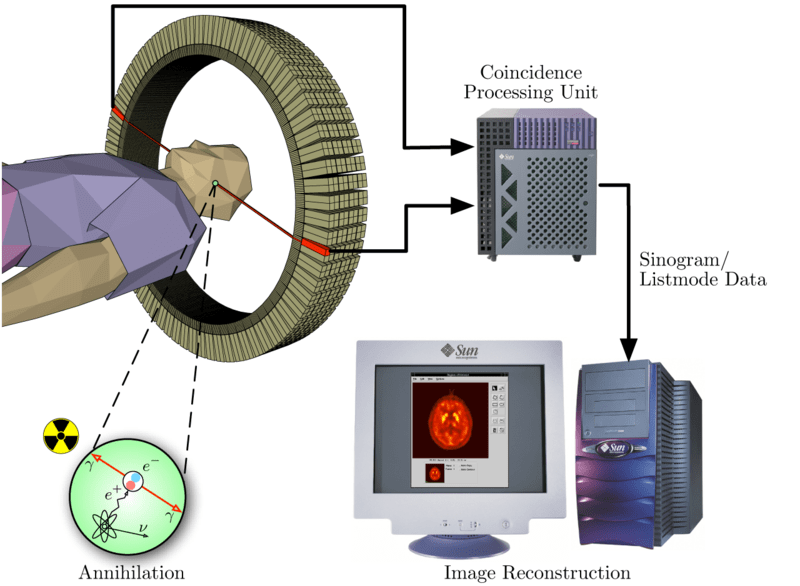

Llegamos por fin al núcleo de la cuestión: se introduce a la persona en el detector, que tiene uno o más anillos capaces de detectar el impacto de fotones muy energéticos. Cuando los átomos inestables empiezan a desintegrarse, emiten positrones dentro de las células… pero las células están hechas de materia normal, con multitud de electrones rodeando todos los átomos. El positrón creado, en un abrir y cerrar de ojos, choca con un electrón y ambas partículas se desintegran, produciendo dos fotones con muchísima energía (radiación gamma). Pero recuerda lo que dije antes sobre los dos fotones: deben salir en sentidos opuestos; sus trayectorias forman más o menos 180°. Por cierto, esto significa que si has sido objeto de una tomografía de este tipo has tenido antimateria en el interior de tu cuerpo, en forma de positrones, aunque sea durante unos milisegundos.

De modo que el anillo que rodea al paciente detecta dos fotones prácticamente a la vez (la luz recorre esa distancia en tiempos pequeñísimos), y uniendo ambos impactos con una línea imaginaria tenemos las posibles localizaciones del positrón responsable. Como los átomos están desintegrándose todo el tiempo, los anillos recogen pares de fotones continuamente, y cruzando las líneas imaginarias que unen cada par de fotones pueden calcular no ya una línea, sino un punto: cada par de líneas que se cruce (o casi se cruce) identifica células emisoras de positrones, es decir, células “marcadas” con la sustancia inestable. Aquí tienes un diagrama que debería aclarar lo que intento decir (muestra la detección de un par de fotones):